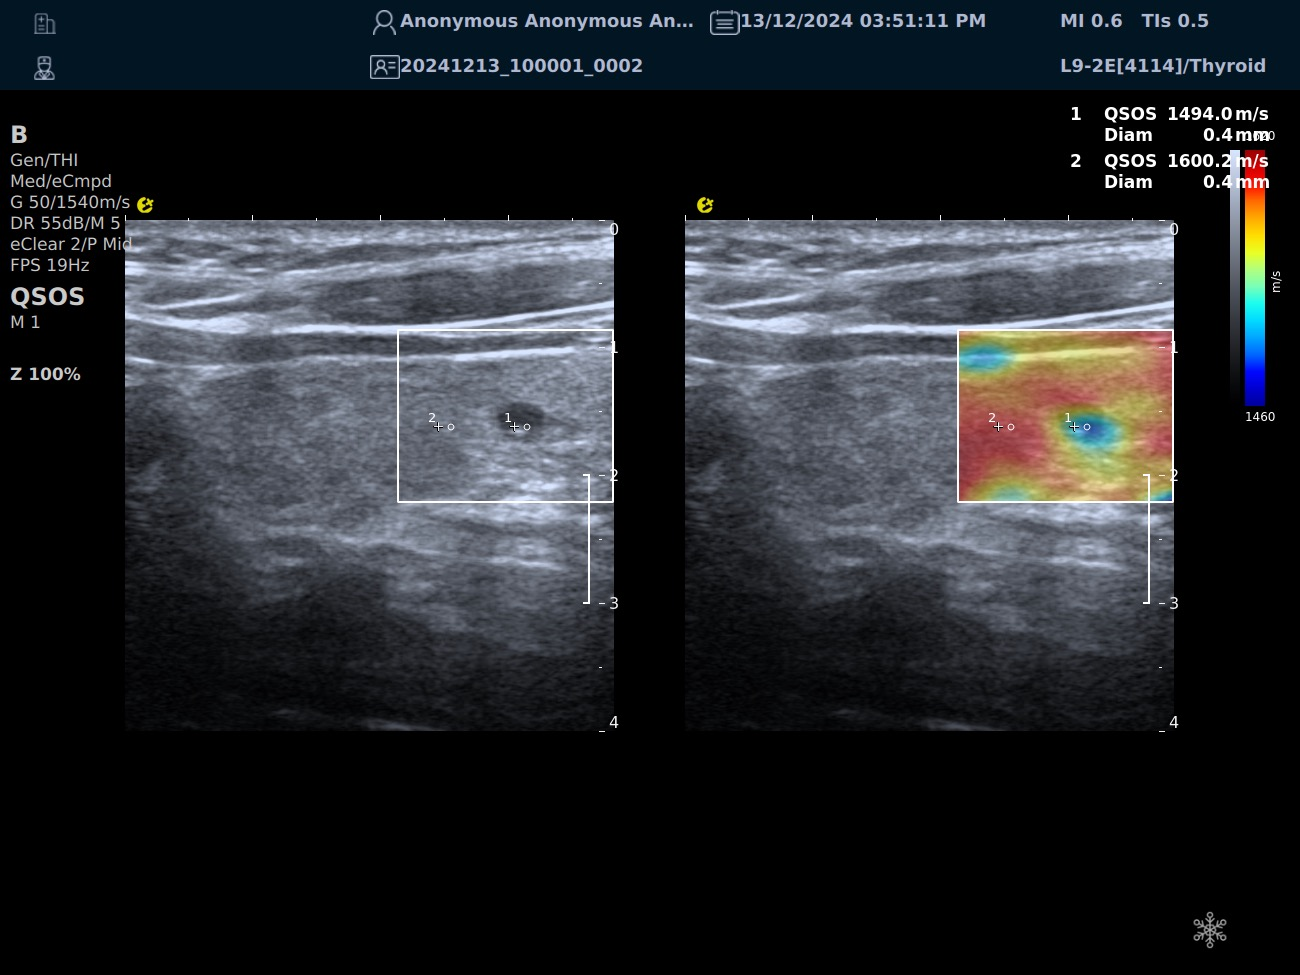

QSOS声速定量成像

测量原理

QSOS声速成像技术利用声波在组织中的传播速度差异性,计算不同位置的声速值,反映组织的物理特性。

成像过程

利用超声探头发射超声波脉冲,分析反射信号的时间延迟,确定声波传播路径和速度,构建声速分布图像。

图像显示

QSOS技术采用彩色编码显示声速图像,不同颜色代表不同声速值,便于医生识别病变部位和测量。

技术优势

?精准定量反映组织特性,成像更敏锐?彩色编码直观显示,轻松发现异常?捕捉声速差异,早期、微小病变更易察觉

肌骨领域的应用

?精准定位损伤部位?判断损伤严重程度?监测肌肉营养?评估肌少症?骨质疏松评估